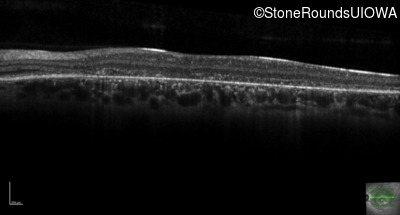

Optical Coherence Tomography - Right - 20/200 -3

Exemplar / OCT Stack

Optical Coherence Tomography - Left - 20/200 -2